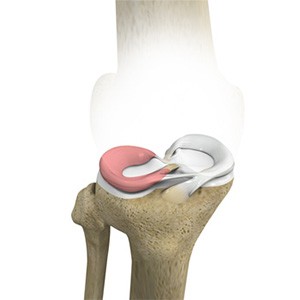

Picture of Meniscal Tears

Meniscal Tears

A meniscal tear is a common knee injury in athletes, especially those involved in contact sports. A sudden bend or twist in your knee causes the meniscus to tear. Elderly people are more prone to degenerative meniscal tears as the cartilage wears out and weakens with age.